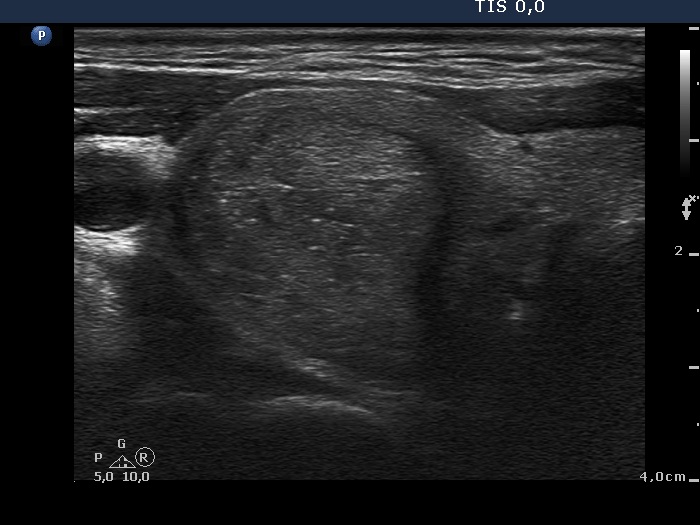

Benign hyperplastic nodules (histological diagnosis) - case cons 024 |

There are pale lines and granules within the nodule - these figures correspond to a connective tissue. The three granules are probably also presentations of a connective tissue.